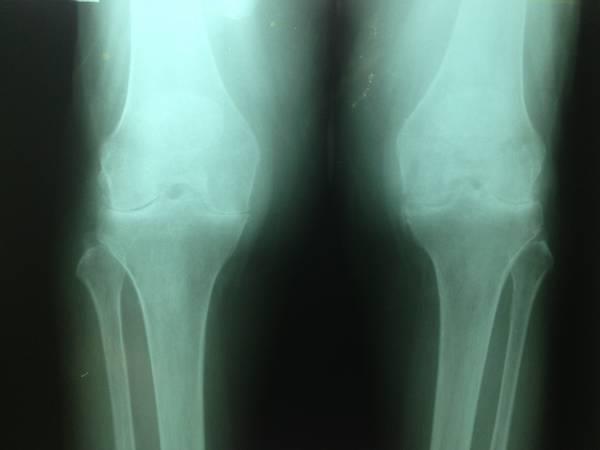

The orthopedic doctor is also the person to order a range of

tests, such as x-rays, MRIs, CT scans if deemed necessary, and other types of

imaging procedures since we, ourselves, can interpret them.